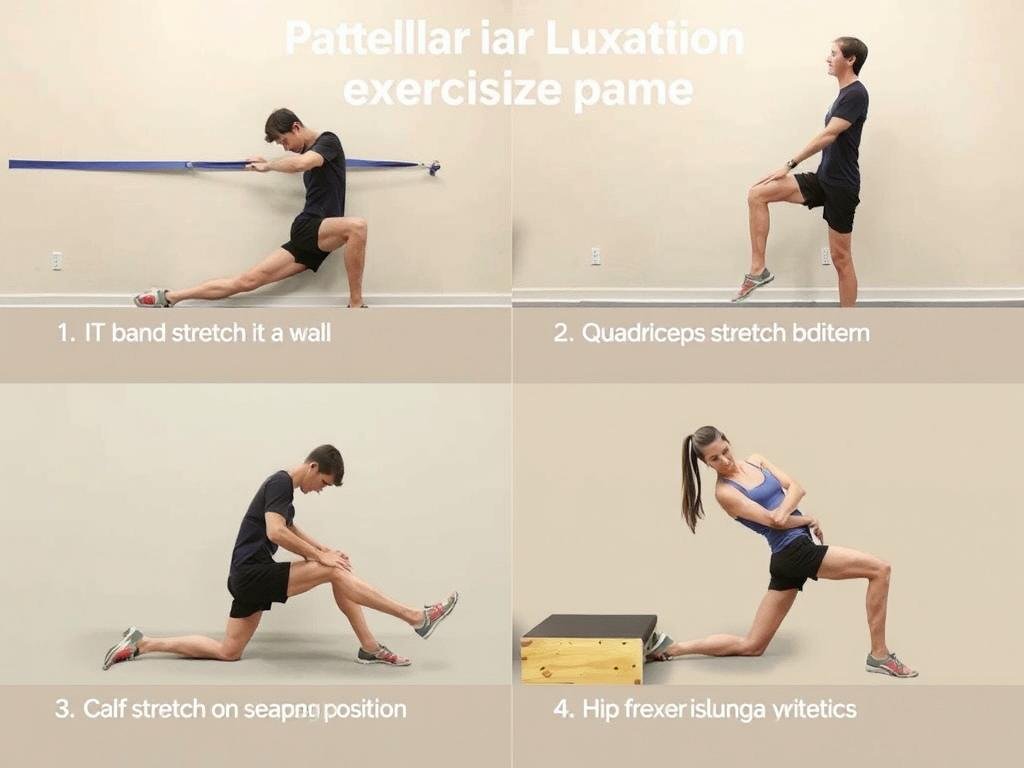

Dehnübungen

- Dehnung des Tractus iliotibialis: Reduziert seitlichen Zug

- Dehnung der Oberschenkelvorderseite: Verbessert die Beweglichkeit

- Dehnung der Wadenmuskulatur: Optimiert die Beinachse

- Dehnung der Hüftbeuger: Verbessert die Beckenstellung

Wichtige Dehnübungen zur Prävention von Patellaluxationen: Tractus iliotibialis, Quadrizeps, Wade und Hüftbeuger